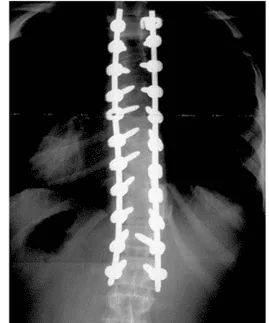

Surgery with Rods and Screws

This option should be the last resort or for those curves that are just progressing to fast especially at a young age or causing distress to organs. While the special exercises and braces are effective for most people, there are instances where we just can’t help. I’ve had patients like this and the rods and screws do change a persons life. Not to say they can’t have a normal life, but fusing your spine will be a challenge in their adult life at some point.